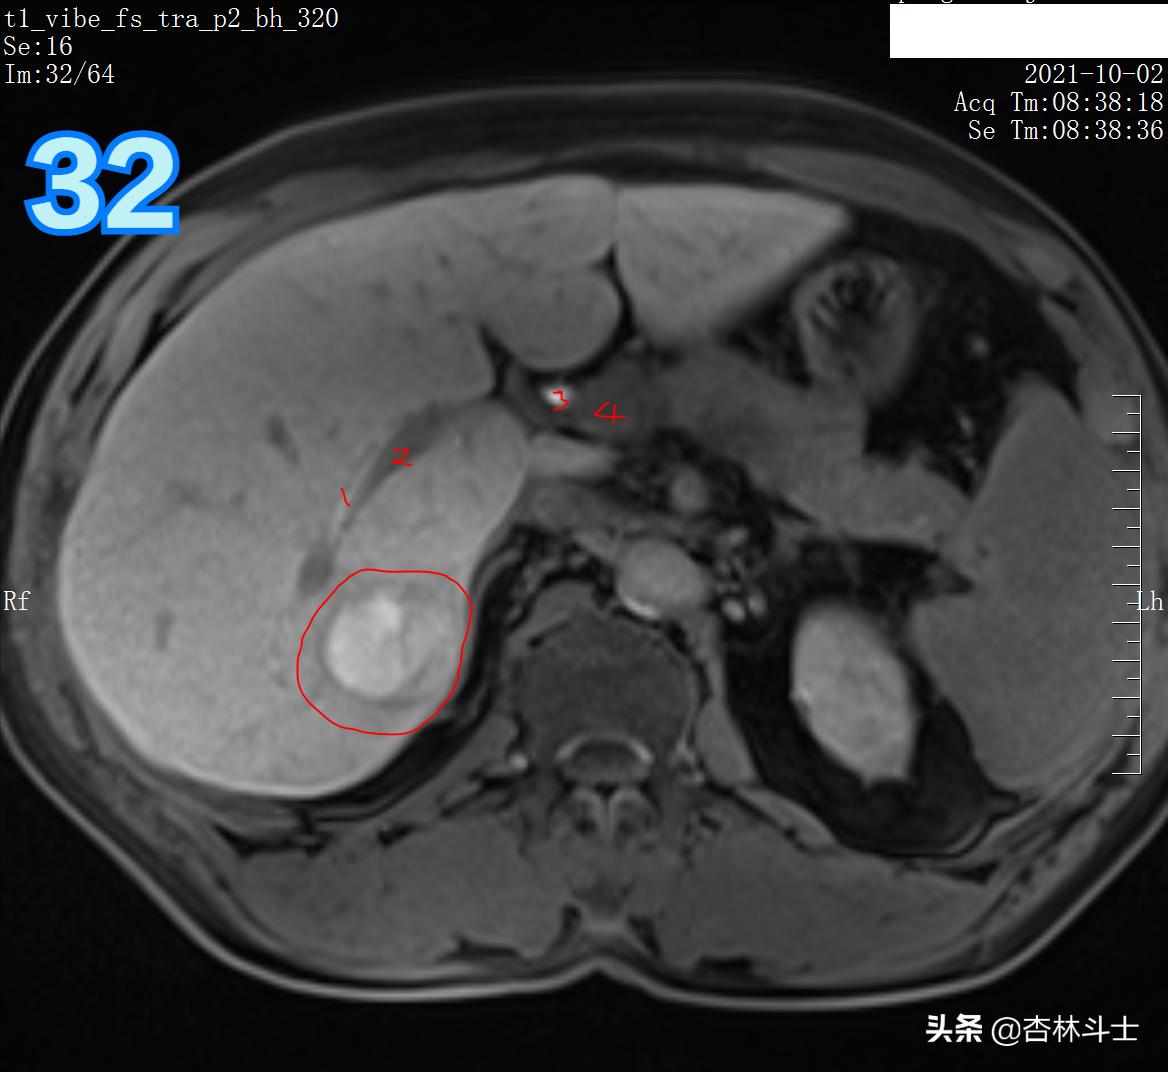

T1压脂肝胆特异期

图31 1、右肝管 2、左肝管

图32 1右肝管 2、门静脉右支 3、肝总管 4、门静脉主干

总结:10月份复查,肝右后叶下段新发一个直径约1㎝的结节,T1呈等信号,T2呈稍高信号,弥散加权序列可见弥散明显受限,增强动脉期明显均匀强化,门静脉期出现对比剂廓清,呈略低信号,平衡期信号进一步减低,肝胆特异期未见特异性对比剂摄取呈低信号。增强特征为典型的“快进快出”,影像学上典型的肝细胞癌表现。